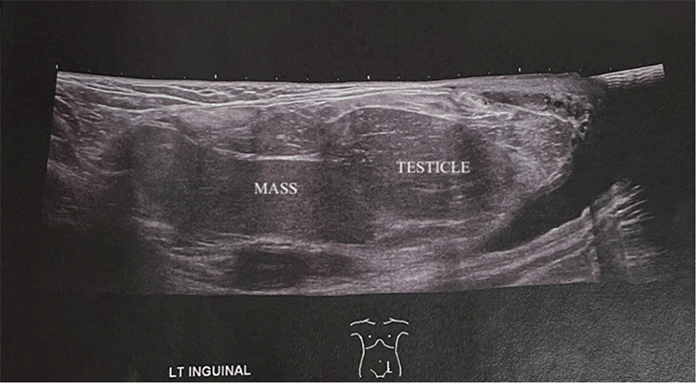

A scrotal ultrasound was performed to differentiate between a recurrent spermatocele and an inguinal hernia. The radiologist interpreted the ultrasound as a large, adipose-containing inguinal hernia (Figure 1). No scrotal lipoma or suspicious adipose mass was identified on ultrasound, so no further imaging was suggested. Additionally, the ultrasound noted atrophy of the left testicle compared to a previous ultrasound performed in 2016 (Figure 2). Based on these findings, the patient to our office for surgical repair of a presumed inguinal hernia.

Figure 1. Scrotal Ultrasound of Testicular Mass (left inguinal view). Published with Permission.